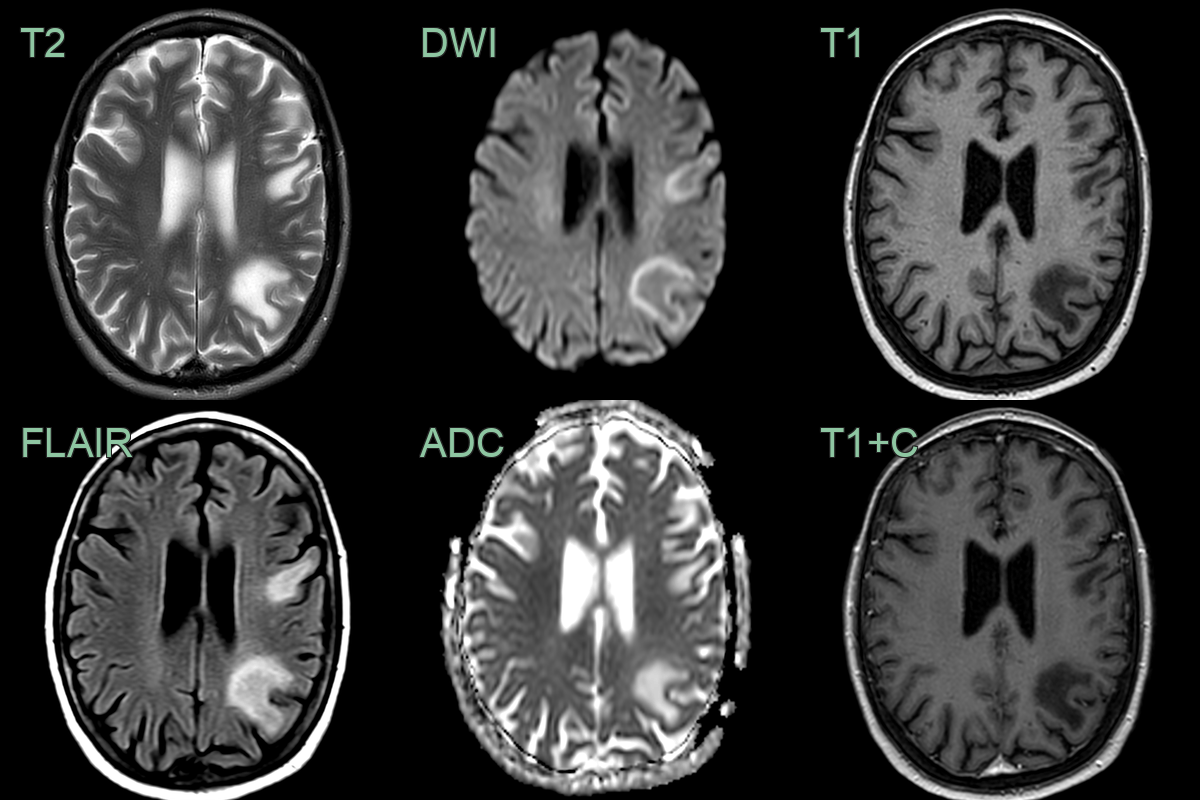

- 75-year-old patient on immunosuppression for rhematoid arthritis presented with subacute cerebellar ataxia.

- MRI showed a T2 and diffusion-weighted hyperintensity in the cerebellar white matter without enhancement.

- JC virus was positive and the lesions regressed after cessation of immunosuppressants.